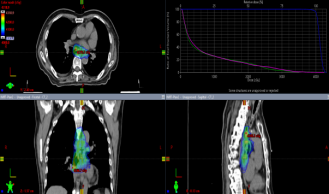

Photon Volumetric Modulated Arc Therapy (VMAT) Plan Diagram

Treatment Planning Image for Carbon Ion Radiotherapy